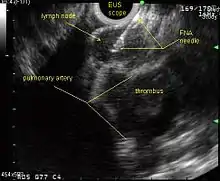

Endoscopic ultrasound (EUS) is an endoscopic technique where a miniaturized ultrasound probe is passed through the mouth into the upper gastrointestinal tract to investigate organs and structures close to the esophagus, stomach, or duodenum, such as the lung. In 1993, Wiersema published the first description of EUS to diagnose and stage lung cancer,[27] done by advancing a fine needle through the esophagus into adjacent lymph nodes. Numerous subsequent studies have shown this general methodology to be effective, very safe, minimally invasive, and very well tolerated. Given these advantages, many authorities think that EUS together with endobronchial ultrasound (EBUS) enhances lung cancer diagnosis and staging.[28]

Endoscopic ultrasound (EUS)

EUS can reliably reach the lymph node stations 5, 7, 8 and 9. In the superior mediastinum the trachea is somewhat to the right of the esophagus which makes it often possible to reach left-sided area 2 and 4 lymph nodes and, less often, right sided paratracheal lymph nodes.[29] In general, EUS is most appropriate for evaluation of the posterior inferior mediastinum while mediastinoscopy or EBUS are best for the anterior superior mediastinum. The feasibility of EUS-FNA of aorto-pulmonary space (subaortic) lymph nodes (station 5) is a major advantage of EUS. Evaluation of this station has traditionally required a paramedian mediastinotomy (Chamberlain procedure). EUS can easily sample celiac lymph nodes, which cannot be reached by the other mediastinal staging methods. In one recent study an unexpectedly high incidence of celiac lymph node metastasis (11%) was noted.[30] EUS can also be used to biopsy potential left adrenal metastases, whereas the right adrenal gland is mostly inaccessible.[31]

EUS-FNA and EBUS-FNA are complementary techniques. EUS has the highest yield in the posterior inferior mediastinum, and EBUS is strongest for the superior anterior mediastinum. Some lymph node stations can only be accessed by one method and not the other (for example, station 2 and 4 L and 3 are hard or impossible to see by EUS, stations 5 and 8 cannot be biopsied by EBUS). Together, EBUS and EUS cover the entire mediastinum (except possibly station 6) and complete mediastinal staging should be possible with a combination of these two procedures. This combination could conceptually eliminate the need for most surgical mediastinoscopies and in fact be more comprehensive.